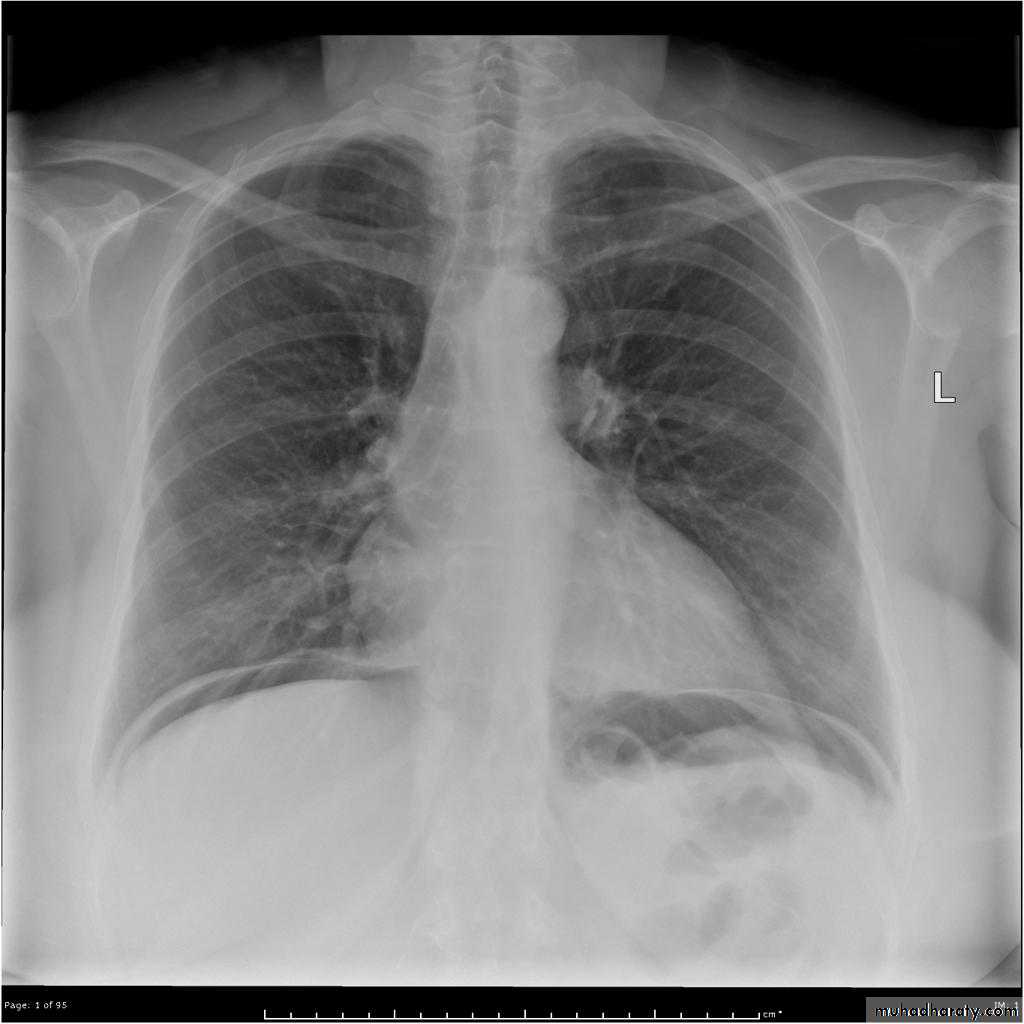

• Radiographic signs of free gas:

• Erect CXR: gas beneath diaphragm (crescent shape).• Supine abdomen: gas outlines anatomical structures, such as the liver, falciform ligament and spleen; bowel walls are seen as white lines outlined by gas on both sides, i.e. inside and outside the bowel lumen (Rigler's sign).

• Free gas is also identified on erect abdomen film.

• If the patient is too ill to stand then either decubitus or shoot-through lateral films can be performed.